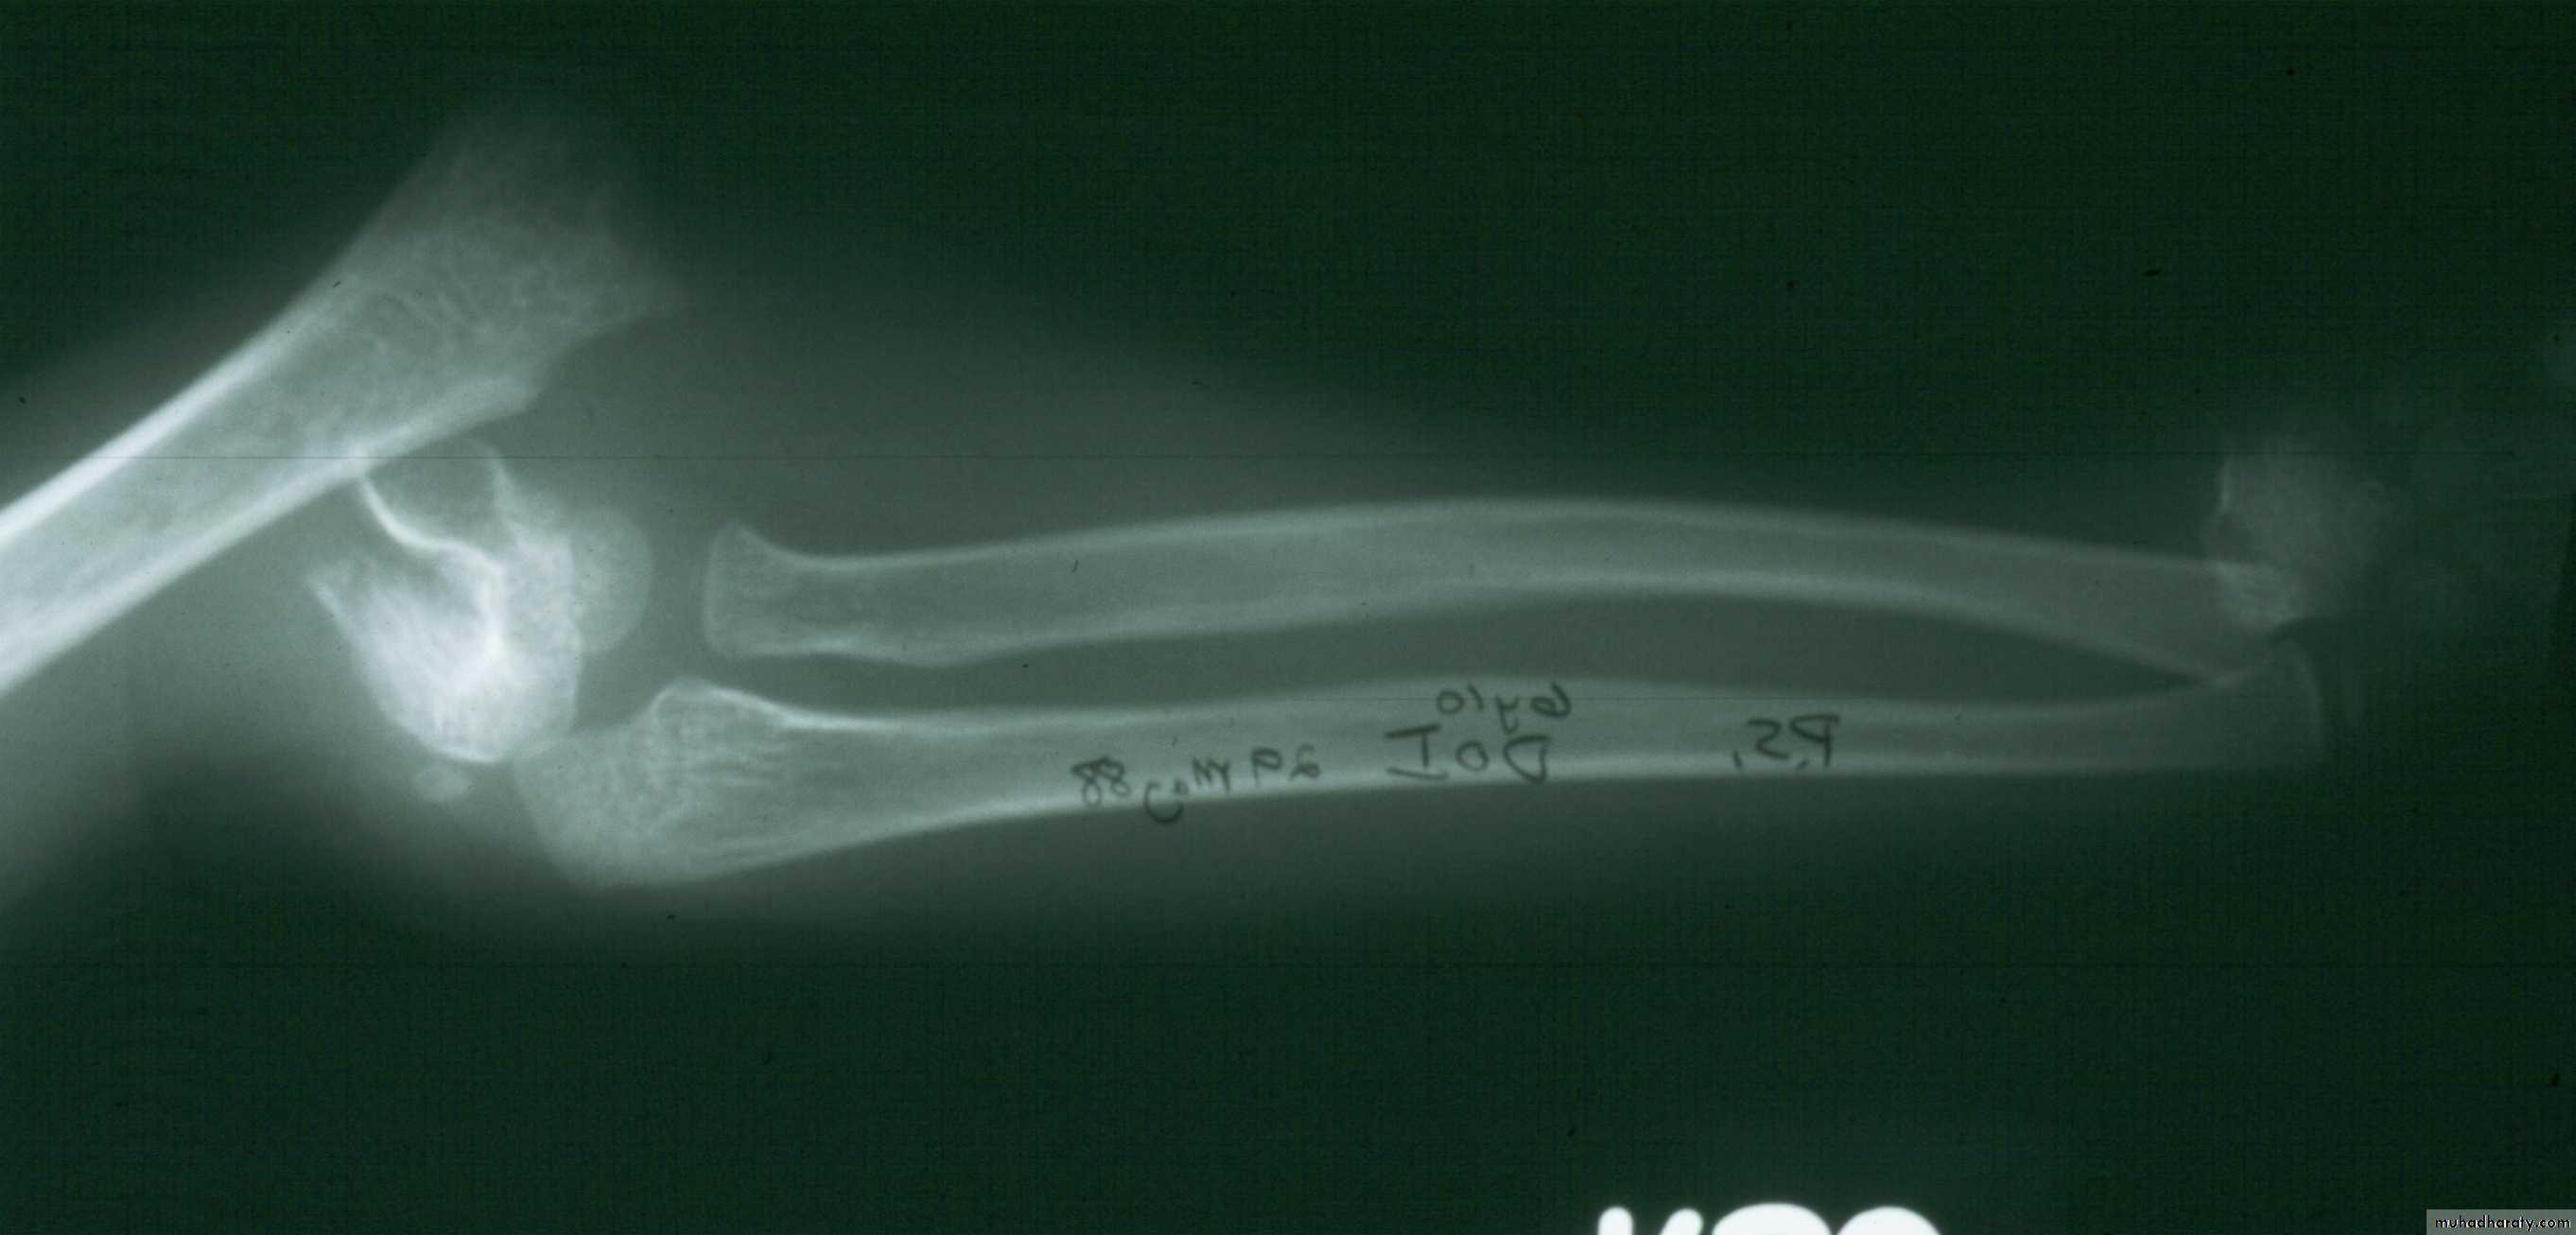

Ipsilateral shaft fractures

Yes. One has to establish a lever arm first.

12

1

2

In what order do they need

to be stabilized?

Distal radius